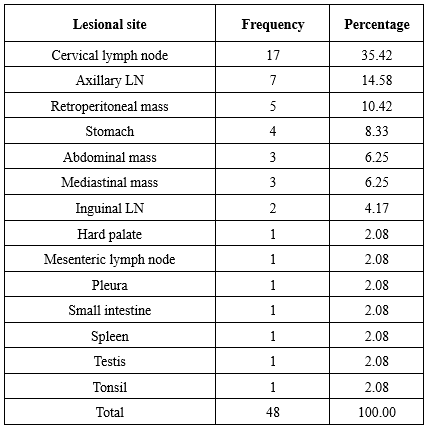

On histopathological evaluation, non-Hodgkin lymphoma without further subtyping was the most common diagnosis (33/48 = 68.75%). Among cases where subtyping was performed based on histomorphology, follicular lymphoma (3/48 = 6.25%) and diffuse large B-cell lymphoma (DLBCL) (3/48 = 6.25%) were equally common. Diagnostic frequencies are presented in Table 4. Representative histopathological images of DLBCL and follicular lymphoma are shown in Figure 1 and Figure 2, respectively.

On histopathological evaluation, non-Hodgkin lymphoma without further subtyping was the most common diagnosis (33/48 = 68.75%). Among cases where subtyping was performed based on histomorphology, follicular lymphoma (3/48 = 6.25%) and diffuse large B-cell lymphoma (DLBCL) (3/48 = 6.25%) were equally common. Diagnostic frequencies are presented in Table 4. Representative histopathological images of DLBCL and follicular lymphoma are shown in Figure 1 and Figure 2, respectively.